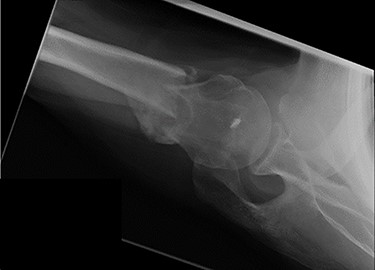

An X-ray of the left shoulder was performed, which revealed acceptable positioning of the fracture. Following a discussion with the patient, a mutual decision was made to manage the injury non-operatively and he was discharged with a collar and cuff sling. Subsequent clinical and radiological review at 1 week and 2 weeks post-injury showed the soft tissues to be healing well and the fracture to be well-positioned (Figs 5 and 6).

Antero-posterior view X-ray taken 1 week post-injury showing acceptable positioning of the fracture.